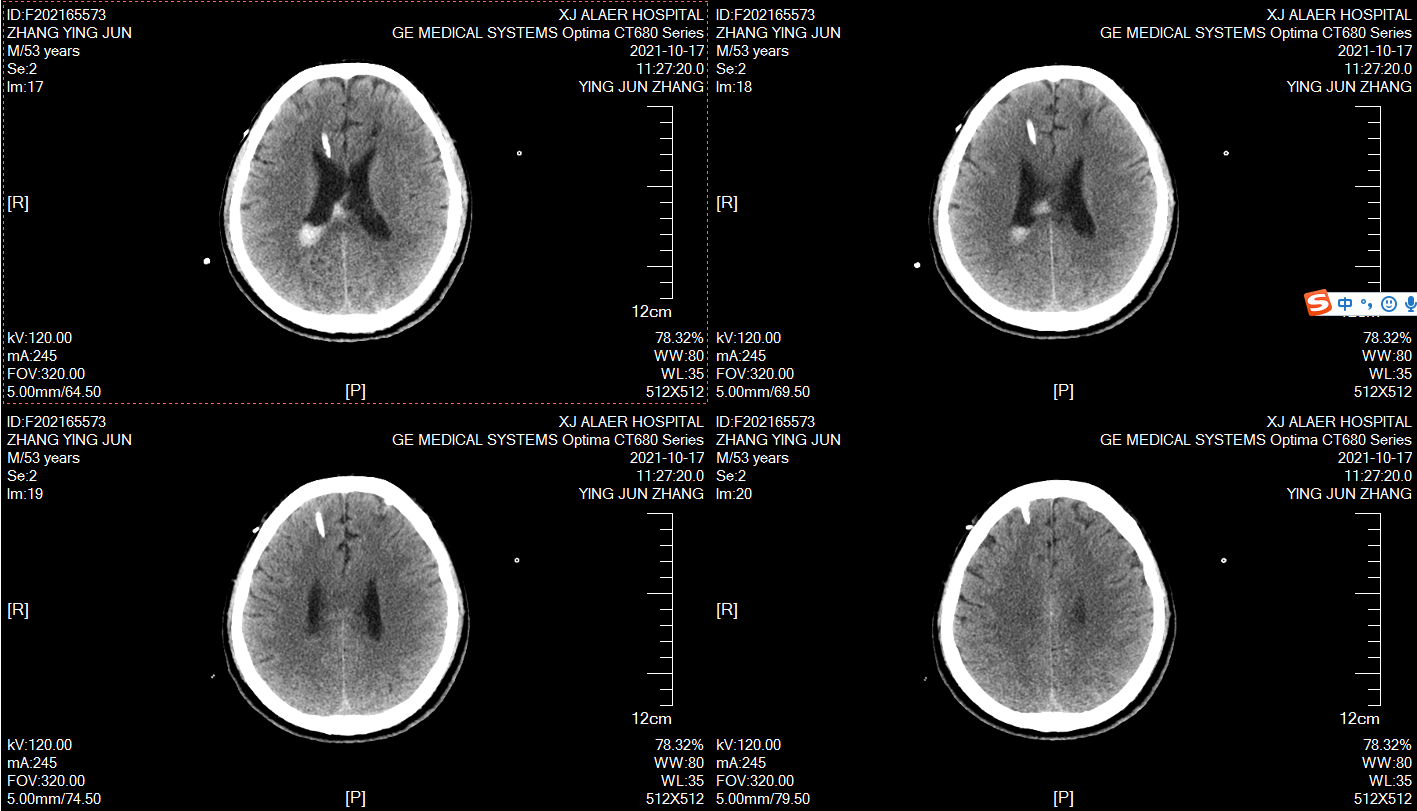

术后复查,尿激酶冲洗!